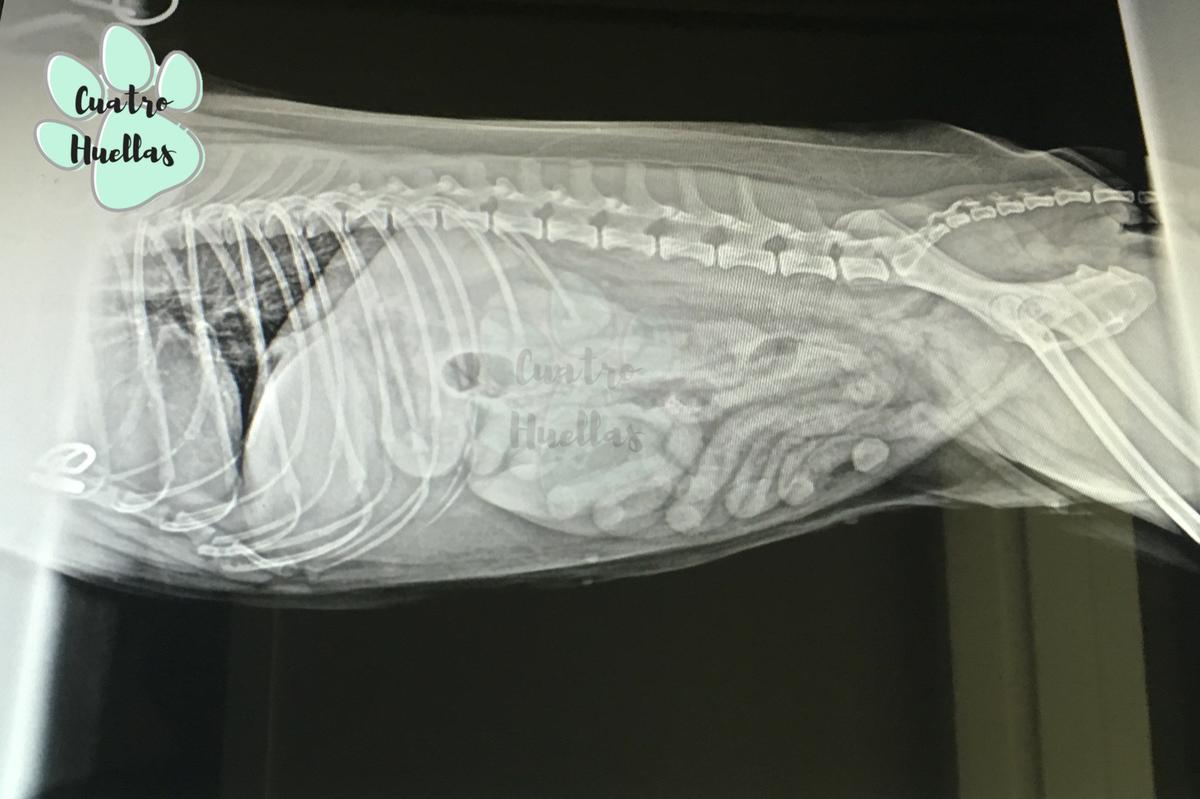

“Solo” una auxiliar fue la que estuvo luchando con él para que se estuviera quieto durante una ecografía y para que no se moviera en la radiografía. “Solo” una auxiliar fue quién hizo la citología para que un veterinario viera si el tumor de tu perro es bueno o malo. “Solo” una auxiliar fue quién controló la anestesia y que tu gato respirara durante toda la cirugía. “Solo” una auxiliar fue quién le hizo la limpieza dental.